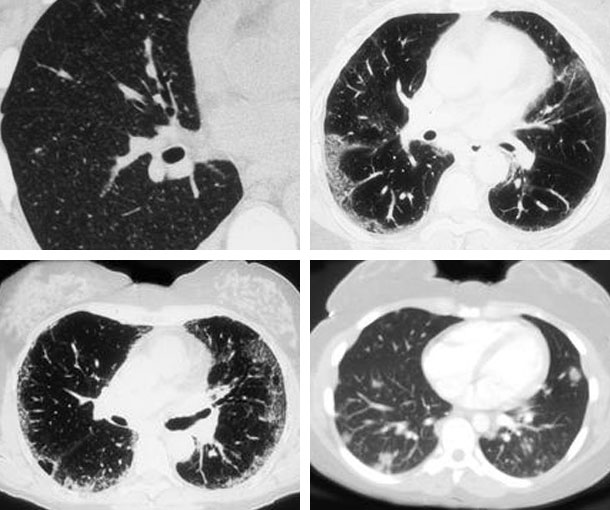

Chest CT Appearances

Cryptogenic Organizing Pneumonia (COP) CT Findings

- Ground glass opacities (GGO)

- Bilateral basal airspace consolidation

- Bronchial wall thickening

- Cylindrical bronchial dilatation

- Centrilobular nodules

- Nodules may be up to 5mm in diameter